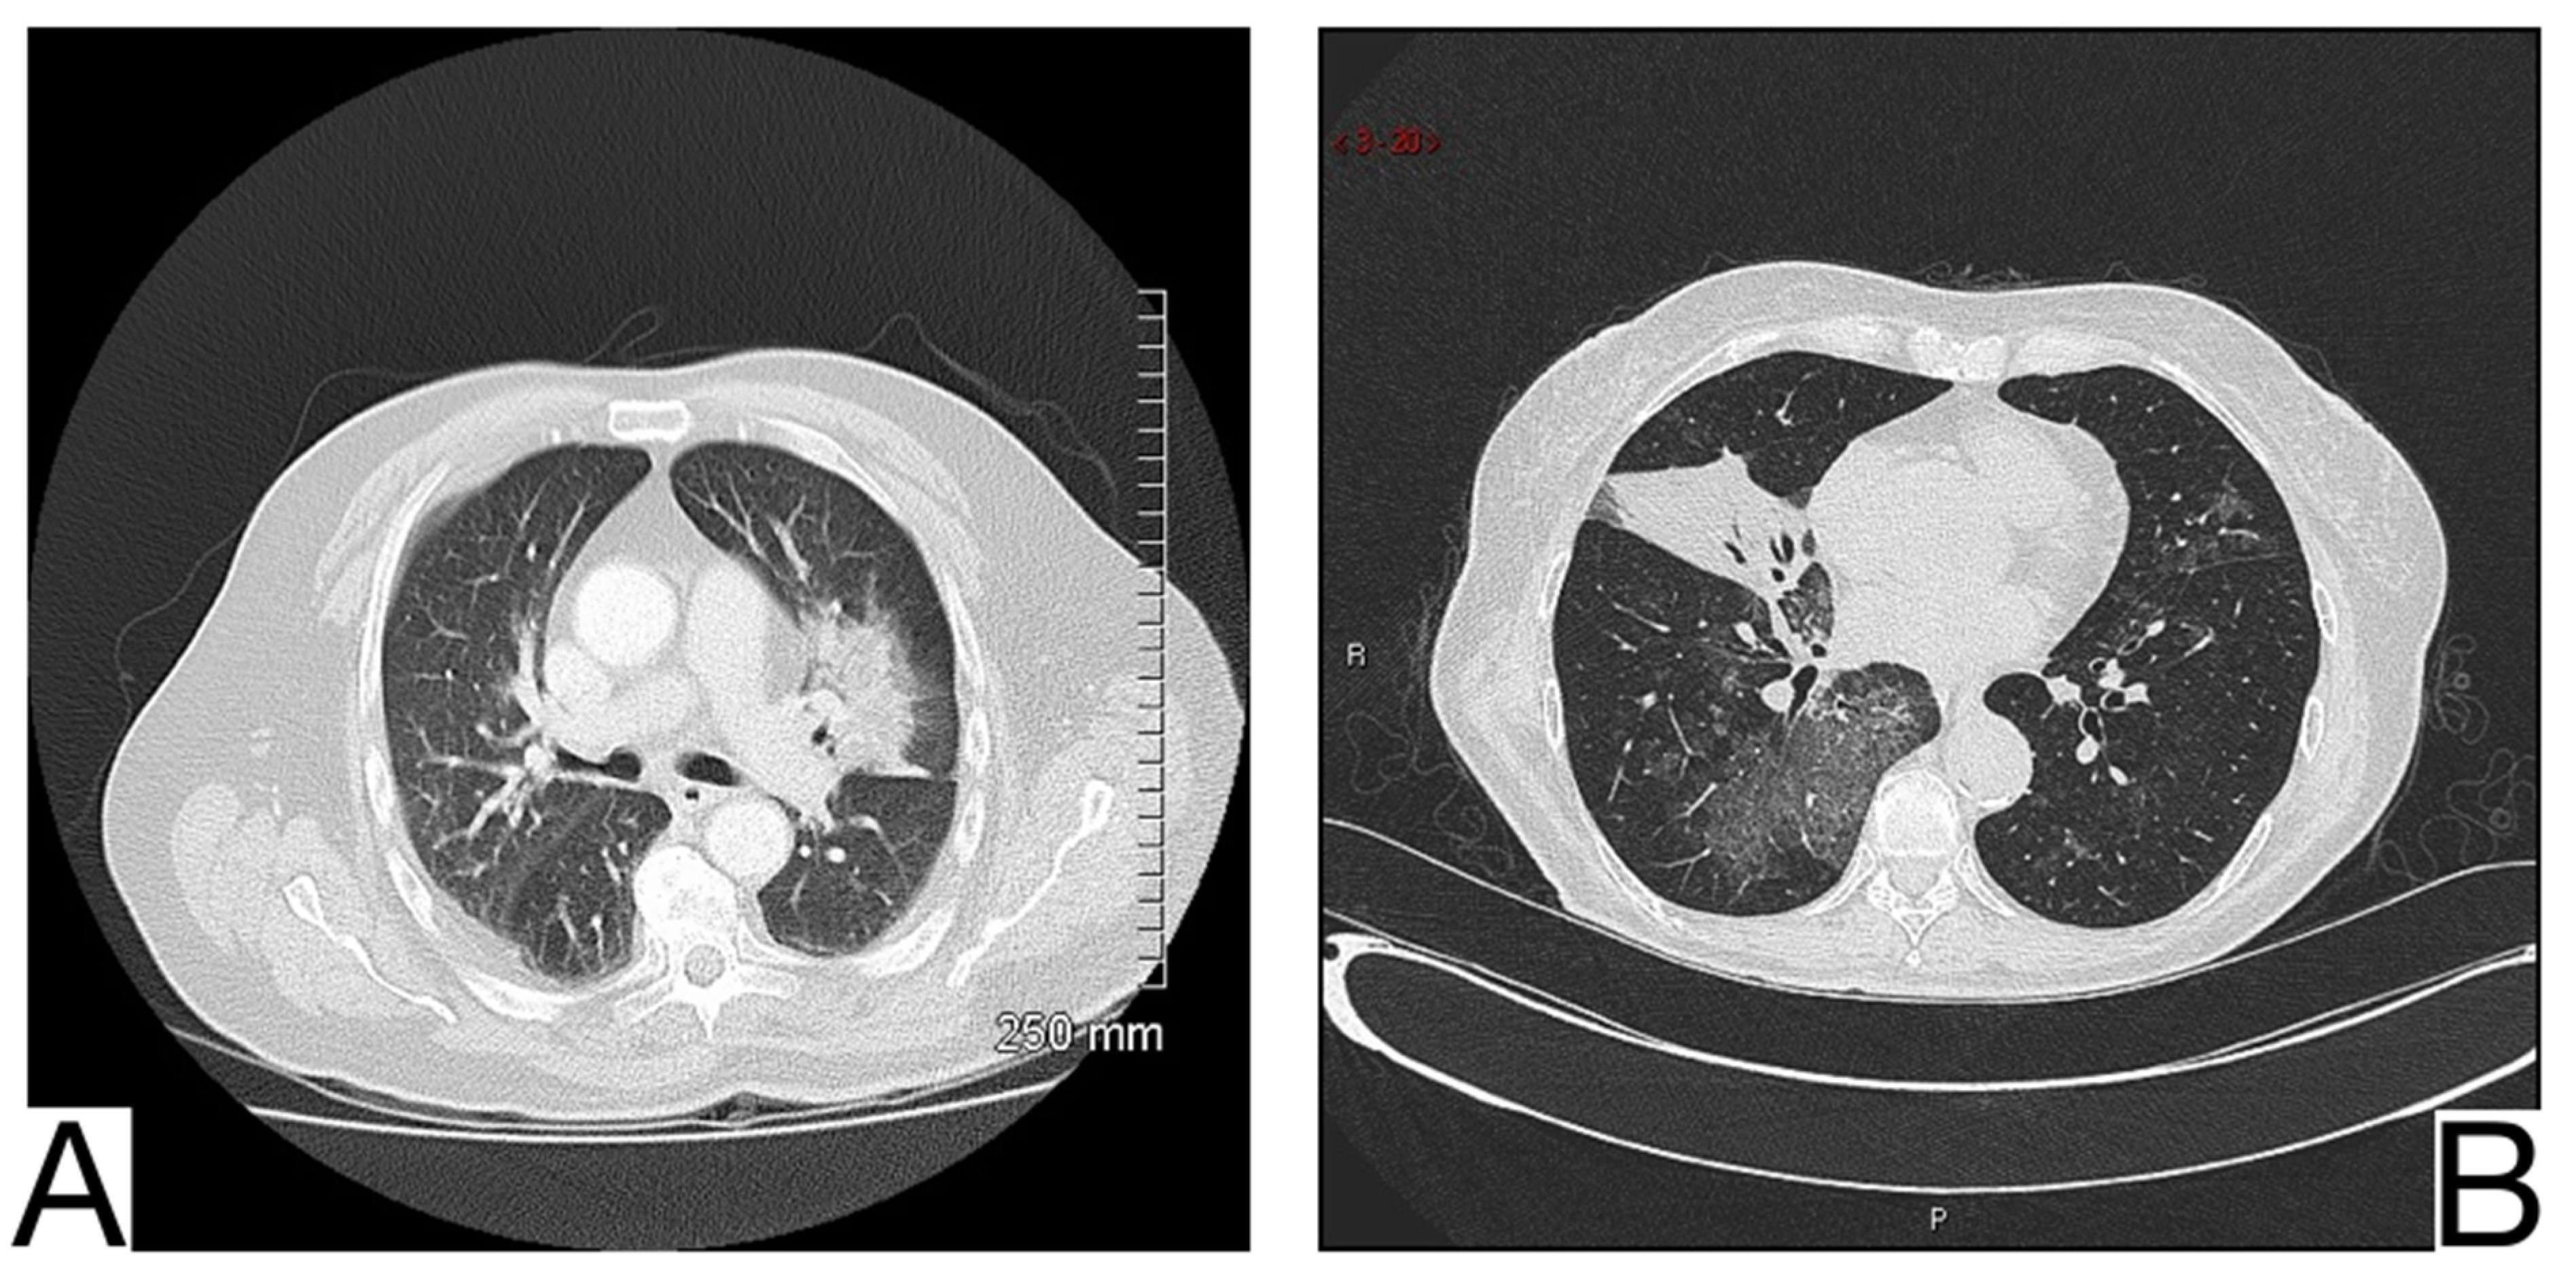

In addition to anamnesis, radiological features (Figure 7A,B) for differential diagnosis are the possible coexistence of ground-glass opacities, pavement, and consolidations with different times of occurrence about COVID-19 pneumonia []; the pattern of crazy pavement—diffuse, bilateral, with central disposition—and ground-glass opacities with subpleural preservation. Condensations are late and generally coexist with pleural effusions; bilateral pleural effusions, more evident in the alveolar phase of edema []; mediastinal lymphadenopathy; cardiomegaly.

Figure 7. Acute pulmonary edema (A). Ground glass opacity in mainly perihilar and dependent distribution (B). Bilateral airspace opacification in central peribronchovascular distribution and smooth interlobular septal thickening (indicating interstitial edema) and moderate bilateral pleural effusion. Note. Case courtesy of The Radswiki, Radiopaedia.org, rID: 1183 (A) and Dr. Rania Adel Anan, Radiopaedia.org, rID: 95825 (B).